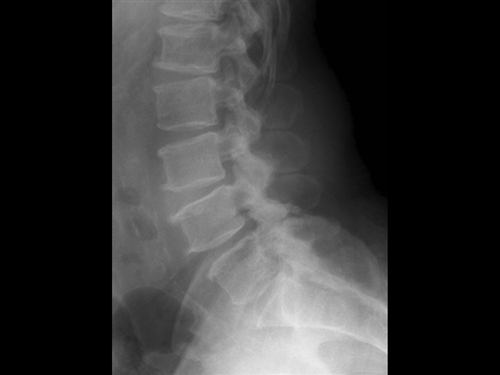

1. A 79-year old man falls sustaining a hyperextension injury to his neck. A lateral radiograph, CT scan and MRI are seen in Figures A through C. On motor examination, he has 3/5 strength in his deltoids, elbow and wrist flexors and extensors. He has 4/5 strength in his hip flexors, knee flexors, extensors, ankle dorsiflexors and plantarflexors. Sensation is preserved in both his upper and lower extremities as well as his sacral segments. Injury to which of the following tracts contributes greatest to his motor function deficits?

FIGURES: A

DISCUSSION: The clinical scenario describes a patient with central cord syndrome, resulting in an injury to his lateral corticospinal tract. Figures A through C show a spondylytic spine with central narrowing and CSF effacement that is worse at the C4-5 level. The lateral corticospinal tract is the main descending motor tract (Illustration A). Its anatomic position places the upper extermity motor tracts at greater risk than the lower extremity tracts. As such, injury to the lateral corticospinal tract is characterized by upper greater than lower extremity involvement and motor deficits being more pronounced than sensory deficits.